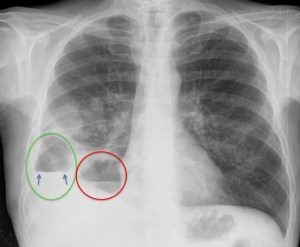

Veámos mejor.

En la placa PA, se observa un encapsulado pleural (verde) y una cavidad parenquimatosa (roo), ambas con nivel hidroaéreo. En el pleural, obsérvese la discordancia del nivel (flechas), tanto en longitud como en densidad, entre las dos proyecciones y borramiento de la pared superior y más posterior en la placa lateral. En la cavidad parénquimatosa, se conserva la misma forma y densidad en las dos proyecciones, con delimitación del controno superior de su pared.